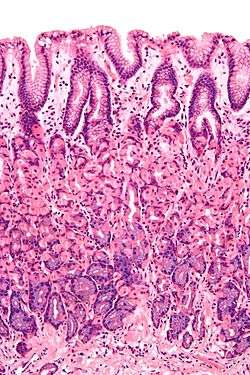

Like the other parts of the gastrointestinal tract, the stomach walls consist of an outer mucosa, and inner submucosa, muscularis externa, and serosa.

The gastric mucosa of the stomach consists of the epithelium and the lamina propria (composed of loose connective tissue), with a thin layer of smooth muscle called the muscularis mucosae separating it from the submucosa beneath. The submucosa lies under the mucosa and consists of fibrous connective tissue, separating the mucosa from the next layer. Meissner's plexus is in this layer. The muscularis externa lies beneath the submucosa, and is unique from other organs of the gastrointestinal tract, consisting of three layers:

The gastrointestinal wall of the stomach.